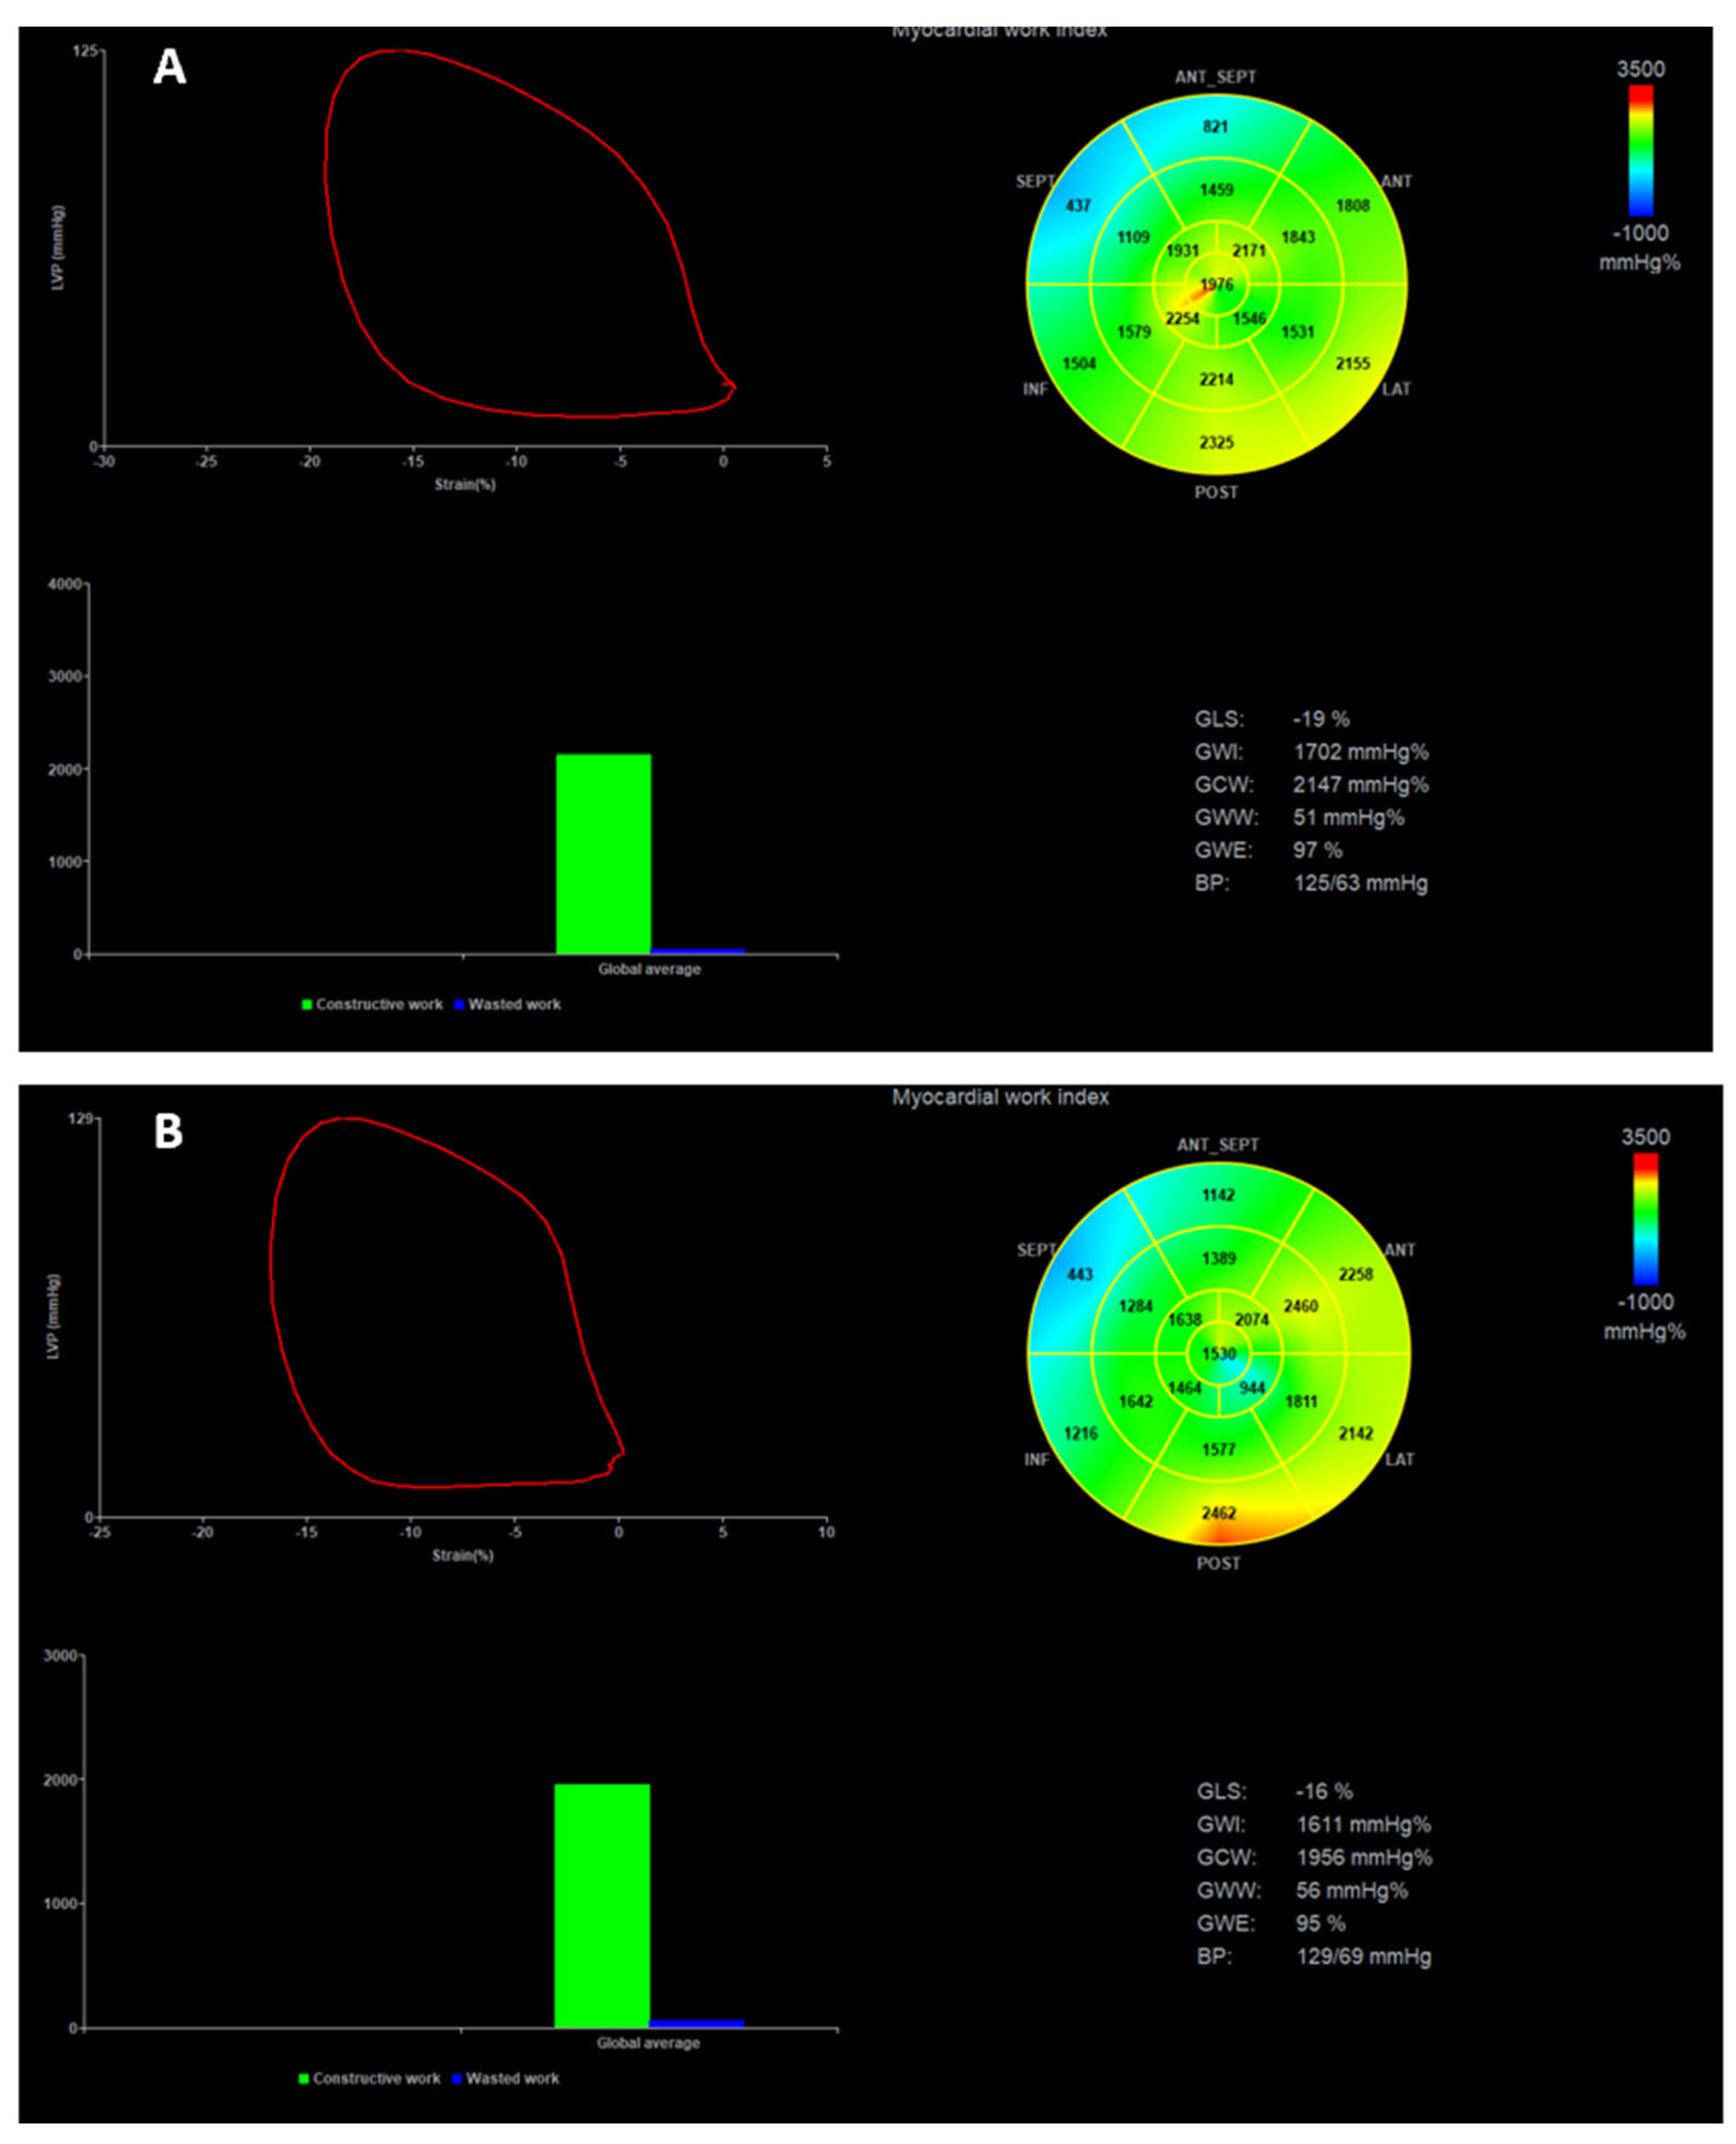

| GLS (%) | -13.28 ± 3.82 | -12.28 ± 3.97 | 0.085 |

| GWI (mmHg%) | 1292.52 ± 608.54 | 1113.89 ± 489.49 | 0.001 |

| GCW (mmHg%) | 1647.15 ± 686.32 | 1438.56 ± 559.95 | 0.009 |

| GWW (mmHg%) | 173.50 ± 126.75 | 202.84 ± 104.63 | 0.062 |

| GWE (mmHg%) | 87.48 ± 8.18 | 85.11 ± 7.73 | 0.007 |